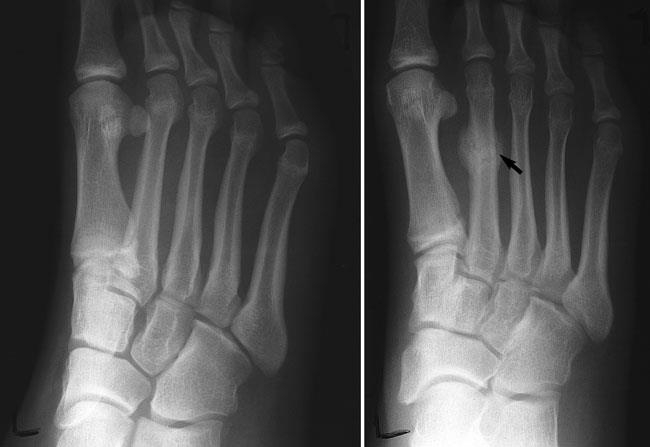

Hairline Fracture - अतिशय बारीक फ्रॅक्चर जे कधी कधी एक्स रे मधून दिसत नाही.